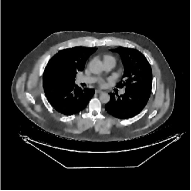

This section compares the reconstruction quality and runtime among the proposed MBIR method, PWLS-ST-, and other three MBIR methods, PWLS-EP, PWLS-DL, and PWLS-ST-. Table I shows that, for both 2D and 3D sparse-view CT reconstructions of the XCAT phantom, the proposed PWLS-ST- model outperforms PWLS-EP and PWLS-ST- in terms of RMSE. In addition, PWLS-ST- using a square transform (of size ) achieves lower RMSE than PWLS-DL using an overcomplete dictionary (of size ) for 2D sparse-view reconstructions. Fig. 3(a) and Fig. 4 show the reconstructed images for 2D and 3D phantom experiments, with different reconstruction models and different number of views. (See the corresponding error maps in the supplement.) The proposed PWLS-ST- consistently gives more accurate image reconstructions compared to other MBIR methods. Specifically, PWLS-ST- has smaller errors in the heart region (see zoom-ins in Fig. 3(a)) of 2D reconstructions than PWLS-DL and PWLS-ST-. In addition, compared to PWLS-ST-, PWLS-DL and PWLS-ST- have some ringing artifacts around the edges with high transition, e.g., edges between air and soft tissues. (See a comparison of profiles of PWLS-ST- and PWLS-ST- in the supplement.) In particular, PWLS-ST- and PWLS-DL give more visible ringing artifacts for 2D reconstruction from fewer views, and PWLS-ST- has these ringing artifacts for 3D reconstructions regardless of the number of views (see zoom-ins in Fig. 4). Table II reports runtimes of different MBIR methods in reconstructing the -views XCAT phantom scan. (FBPConvNet is a non-MBIR method and its runtime for processing a image is approximately one second with a TITAN Xp GPU.) While providing better reconstruction quality, the proposed Algorithm 1 of PWLS-ST- has shorter runtime compared to the algorithms of PWLS-DL and PWLS-ST- in Section III-A. Similar to the PWLS-EP algorithm, the reconstruction time of the PWLS-DL, PWLS-ST-, and PWLS-ST- algorithms can be further reduced by using ordered subsets [51].

| (b) 3D axial cone-beam CT experiments |